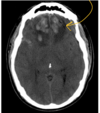

Describe

frontal cerebral contusion